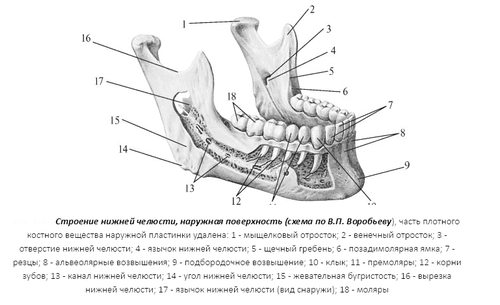

Структура нижньої щелепи

Нижня щелепа - єдина частина черепа, яка може виконувати руху, що стало наслідком тисячолітньої еволюції людини. Це відкрило нашого виду нові можливості, а й доставило деякі неприємності, внаслідок високої рухливості вона стала в більшій мірі схильна до травм, в тому числі і вивихів. Верхню щелепу вивихнути неможливо, її можна тільки зламати, тому що вона нерухома.

Кость нижньої щелепи закінчується скроневим суглобом, який представляє собою ямки в суглобах-скроневої кістки. Висока його рухливість забезпечує нам можливість не тільки жувати їжу, але і спілкуватися між собою. Нижня щелепа може активно рухатися по вертикалі і не так активно по горизонталі.

Вивих відбувається коли зміщується скронево-щелепної суглоб, тобто його головка вистрибує з ямки. Постійні такі травми можуть свідчити про дефекти будови суглоба: або занадто дрібні ямки, або дуже слабкі зв'язки. Якщо зсув тільки часткове, то повернення суглоба в природне положення відбувається без особливих зусиль, такий стан ще називають підвивихи.